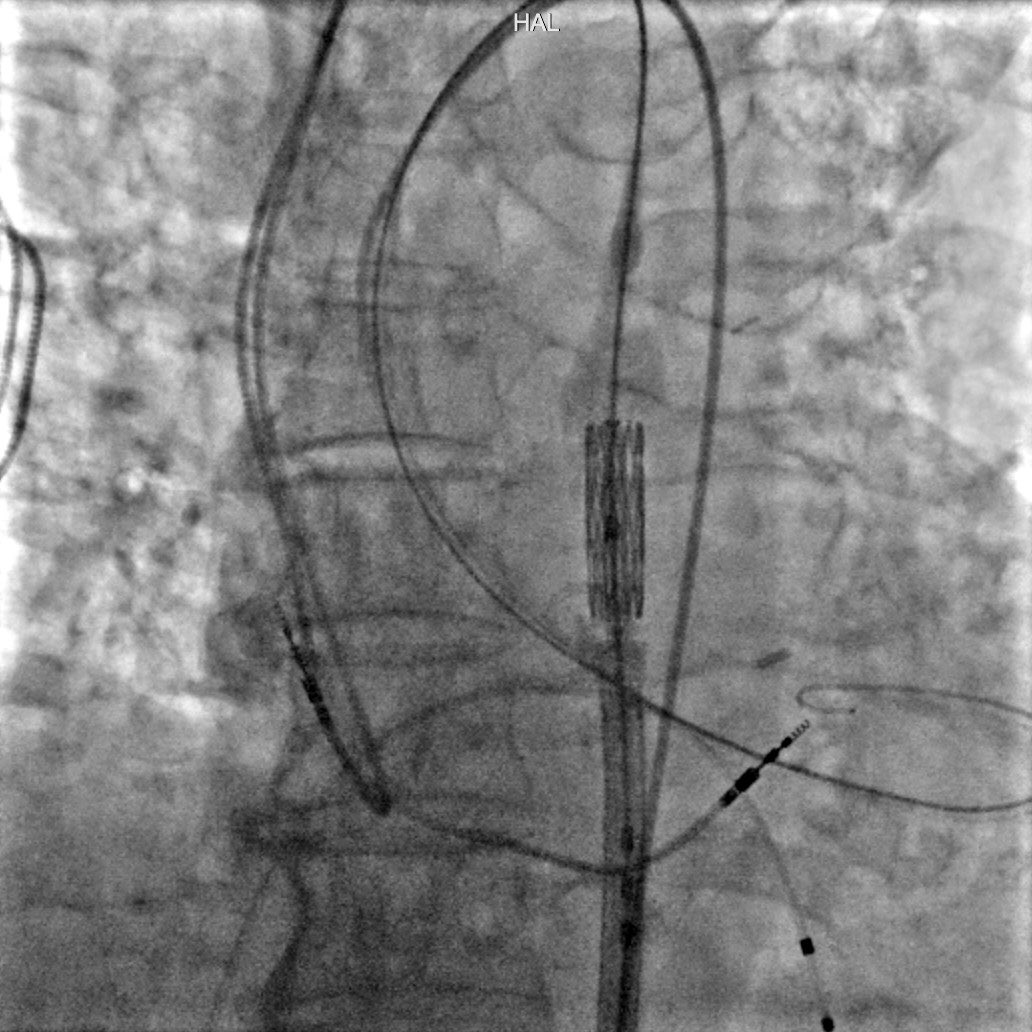

When transfemoral access is not feasible for #TAVI, transcaval access may offer a solution. This case showed a modified #transcaval approach using IVUS to navigate severe aortic calcification, enabling safe valve delivery in a high-risk patient. ow.ly/1O1l50W75hh #EAPCI

When transfemoral access is not feasible for #TAVI, transcaval access may offer a solution.

This case showed a modified #transcaval approach using IVUS to navigate severe aortic calcification, enabling safe valve delivery in a high-risk patient.